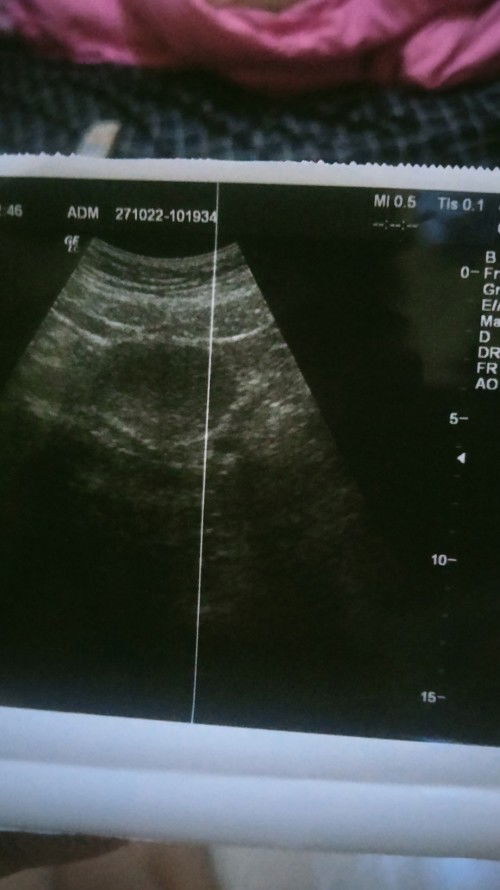

Dari hpht harusnya udh 7 minggu karena berulang kali d tp hasilnya positif, tp tadi di usg baru penebalan dinding rahim katanya, ada yg pernah ngalamin sama kaya aku ga bun? Apa akan menjadi kehamilan? Dan apa boleh sekarang hb sama suami, kasian suami soalnya udh 2 minggu ngajak hb tp saya nya gamau soalnya takut mengganggu ke proses kehamilan saya, maklum anak pertama pengen dijaga banget bun #firstmom #bantusharing #ingintahu